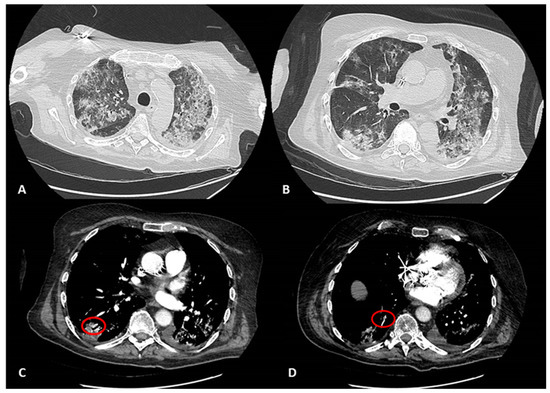

:1. Case Report